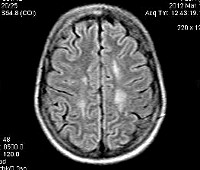

Информация о диссеминированном рассеянном энцефаломиелите